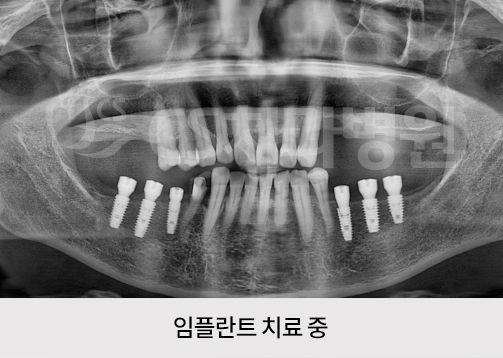

치료기간 : 2021.06.29 ~ 2022.01.17

*실제 본 원에서 치료를 받은 환자의 동의를 얻어 게재하였으며 무단 복제, 사용을 금합니다.

*부작용 고지 : 치료 후 감염, 염증, 연조직 합병증, 출혈, 감각이상 등의 부작용이 있을 수 있습니다.